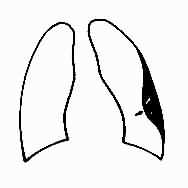

中量积液:液体量较多时,由于液体的重力作用而积聚于胸腔下部的肺四周,表现为下肺野均匀致密,肋膈角完全消失。膈影不清(图3-1-14)。由液体形成的致密影的上缘呈外高内低的斜形弧线。此弧线的形成是由于胸腔内的负压状态、液体的重力、肺组织的弹性、液体的表面张力等作用所致。实际上液体的上缘是等高,但液体的厚度是上薄下厚,液体包绕肺的周围,当摄影时,胸腔外侧处于切线位,该部液体厚度最大,因而形成外侧和下部密度高,内侧和上部密度低。

图3-1-14 右侧胸腔中量积液

右下肺野均匀致密,肋膈角与膈影不能分辨,

上缘模糊不清,心脏左移